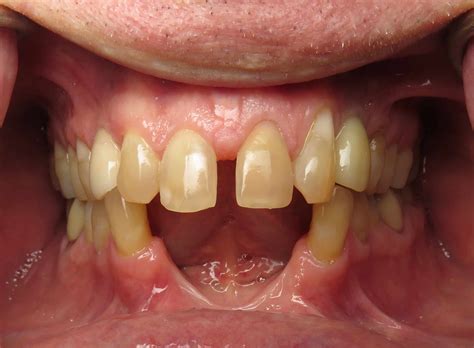

With age, teeth can become more susceptible to wear and tear, decay, and gum disease. Some common age-related dental issues include:

• Tooth Wear: Years of chewing and grinding can wear down the enamel, making teeth more sensitive and prone to decay.

• Gum Disease: As we age, the risk of gum disease increases, which can lead to tooth loss if left untreated.

• Dry Mouth: Certain medications and medical conditions can cause dry mouth, which increases the risk of tooth decay.

Regular dental check-ups and good oral hygiene can help prevent these issues and maintain tooth health.